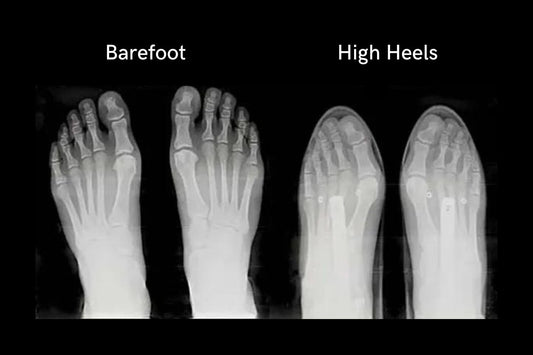

The Hidden Truth About Modern Footwear: Why Your Shoes Might Be Destroying Your Feet The Hidden Truth About Modern Footwear: Why Your Shoes Might Be Destroying Your Feet Did you...